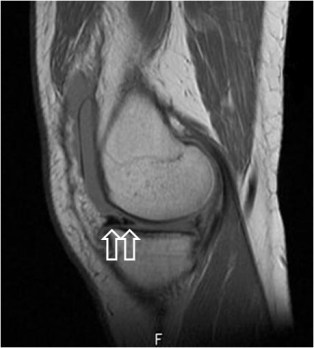

SIGNO DEL DOBLE LIGAMENTO CRUZADO POSTERIOR

Signo de rotura meniscal en los cortes sagitales de Resonancia magnética. El fragmento roto (flecha blanca) se desplaza medialmente y se coloca bajo el ligamento cruzado posterior (flecha roja), dando la imagen de duplicación de éste.